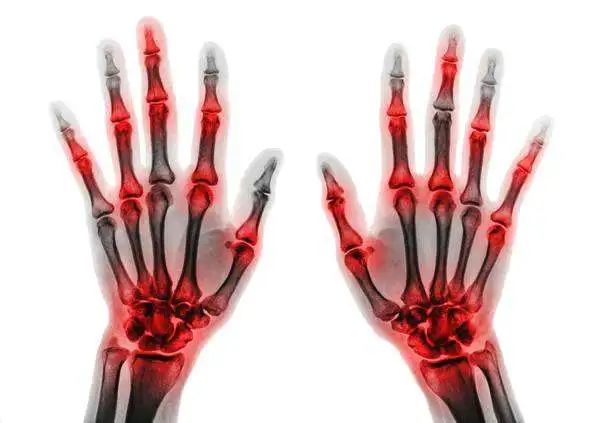

手上出现麻木、刺痛等症状

患者手上出现麻木、刺痛等症状 , 这是早期脑梗的重要征兆之一 , 不免遗憾的是 , 大多数人对这些轻微的症状不当一回事 , 但是 , 如果这时候能及时检查下头部CT , 大多数患者的脑梗塞可能会被提前发现 , 可以得到尽早地治疗 , 有效防止病情恶化 。

脑梗 , 最忌讳的事就是一拖再拖 , 手部出现小症状不及时就医检查 , 等到一侧肢体都不能动弹的时候 , 再去医院治疗 , 那时 , 患者十之八九都会留下脑梗后遗症 。

尤其对于50岁以上的人群和长期吸烟酗酒、高脂肪饮食的人群以及有高血压和糖尿病病史的人群 , 这些都是罹患脑梗的高风险人群 , 更需要时刻注意自己身体发现的异常信号 。